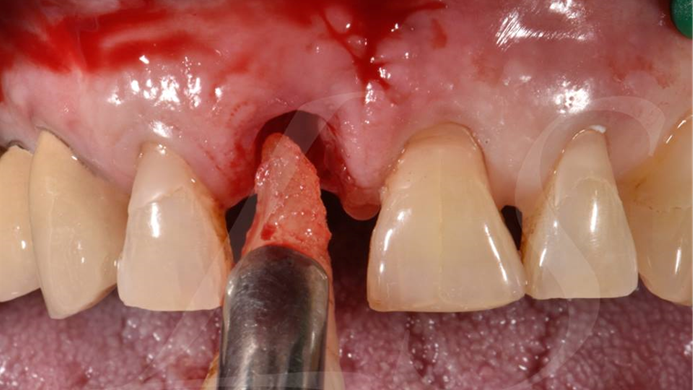

Clinical case: : R2GATE guided surgery & immediate implant placement

- Courtesy of Dr. Kwang Bum Park, Korea -

Dr. Kwang Bum Park, immediate loading, digital guided surgery, digital ONE-DAY implant, maxillary anterior, #21, guided surgery, immediate loading, AnyRidge, R2GATE, Mega ISQ, MEG Torq, R2GATE Full Surgical Kit

implant system, R2GATE Guide, R2GATE full surgical kit, Mega ISQ